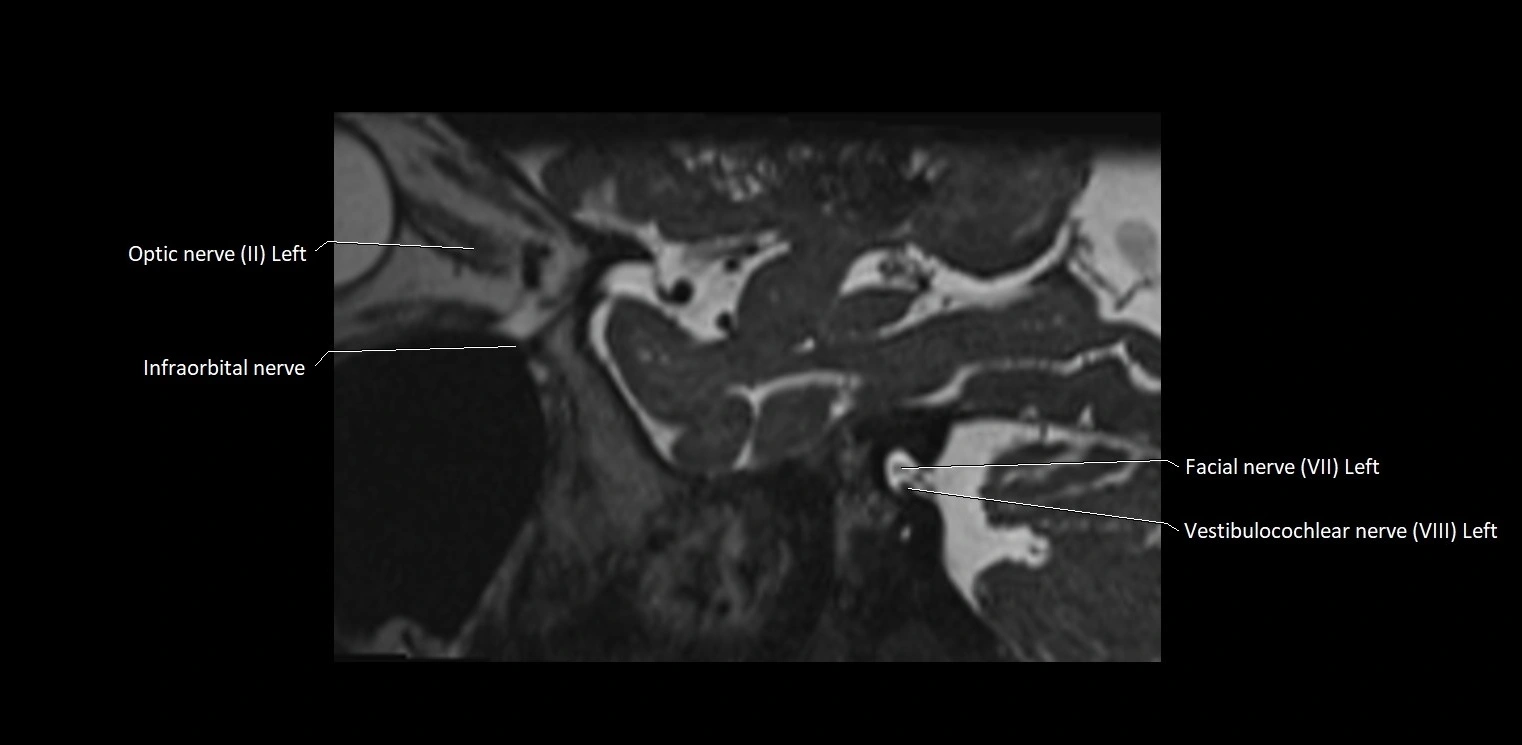

MRI Appearance

• The abducens nerve is a small, thin, linear structure

• Best visualized on high-resolution T2-weighted 3D MRI sequences (e.g., FIESTA or CISS)

• Seen as a hypointense (dark) line running from the brainstem at the pontomedullary junction, traversing the prepontine cistern, and entering Dorello’s canal under the petrosphenoidal ligament, then into the cavernous sinus, and finally the orbit

• May be challenging to visualize in standard MRI due to its small size

• Pathology may be inferred by absence, displacement, or enhancement of the nerve

MRI images

image